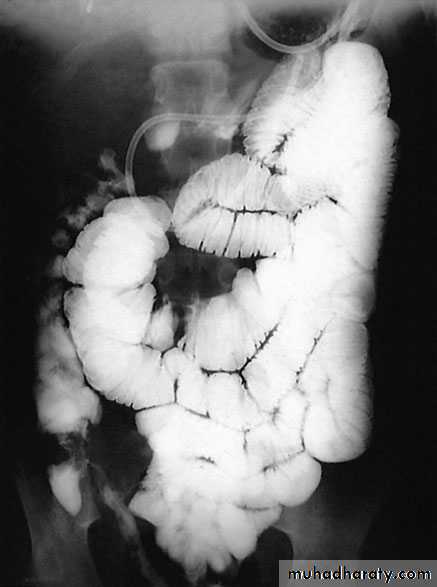

ImagingBarium enema will show similar features to those of colonoscopyin the colon. The best investigation of the small intestine is smallbowel enema . This will show up areas of delay anddilatation. The involved areas tend to be narrowed, irregular and,sometimes, when a length of terminal ileum is involved, theremay be the string sign of Kantor. Sinograms are useful in patientswith enterocutaneous fistulae. CT scans are used in patients withfistulae and those with intra-abdominal abscesses and complexinvolvement .Magnetic resonance imaging (MRI) has been shown to be usefulin assessing perianal disease.